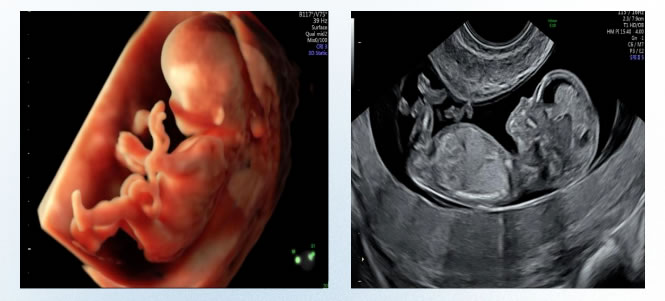

4 III級超聲檢查:孕20-24周

中孕期產前超聲篩查(係統超(chāo)聲檢查),也稱大排畸,主要對胎兒各個解剖(pōu)結構(gòu)及係統進行全麵的(de)結構(gòu)篩查;主要篩(shāi)查九(jiǔ)大類(lèi)致死性胎兒畸形。

第二次超(chāo)聲產前篩查:孕20-24周,係統超聲檢查(產前III級超聲檢查(chá)),也稱大排畸超聲,主要對胎兒各個(gè)解剖(pōu)結構及係統進行全麵的結構篩查;主要篩查九大致死性胎兒畸形。